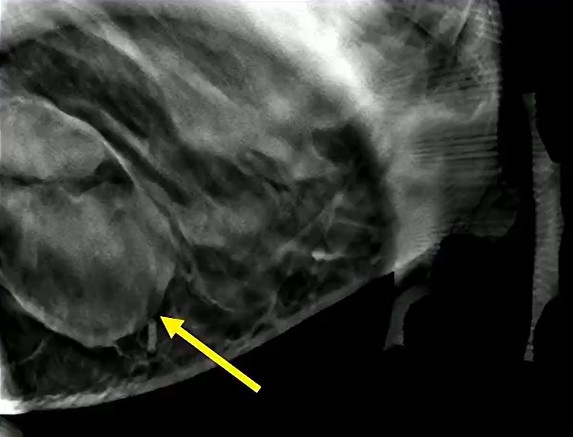

True vs. False Lumen in Acute Aortic Dissection

Look for the beak sign and larger caliber to ID the false; check the arch “wraparound” and calcification patterns for truth.